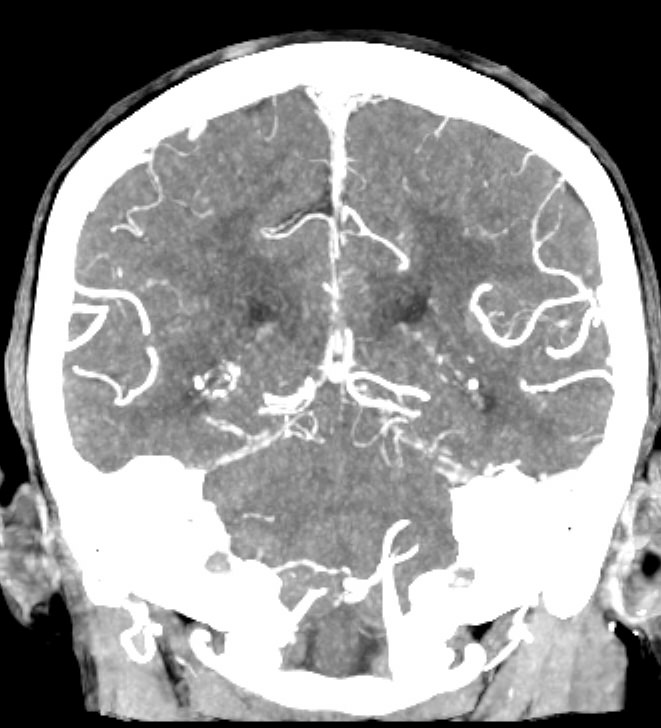

Мультиспиральная компьютерная томография головного мозга относится к лучевым методам исследования и основана на использовании проникающей способности рентгеновских лучей, которые в различной степени поглощаются органами и тканями. Степень поглощения зависит от плотности анатомических структур, благодаря чему можно получить подробные изображения внутренних органов. Во время исследования трубка томографа вращается вокруг пациента и производит снимки поперечного сечения, что позволяет детально визуализировать кости черепа и все структуры головного мозга.

Для улучшения видимости внутричерепных структур применяется методика внутривенного болюсного контрастирования. Во время проведения КТ пациенту в вену вводится йодсодержащее контрастное вещество. Контраст с током крови попадает в патологически измененные участки ткани и очаги, что на снимках придает им яркие отличительные признаки по сравнению с окружающими здоровыми тканями. Контрастирование, в первую очередь, помогает в диагностике опухолевых процессов на ранних стадиях, когда лечение может дать наилучший результат.

В наших медицинских центрах КТ головного мозга с контрастированием проводится на новейших мультиспиральных компьютерных томографах экспертного уровня TOSHIBA AQUILION в различных модификациях. Аппараты снабжены увеличенным количеством сверхчувствительных детекторов, что позволяет при сканировании выполнять множество срезов поперечного сечения с минимальной толщиной среза от 0,5 мм. В результате получаются изображения исследуемой зоны в мельчайших подробностях, которые затем с помощью инновационных цифровых приложений преобразуются в трехмерные пространственные модели головного мозга для более точной диагностики. Помимо высокого качества изображений увеличенное количество детекторов обеспечивает быстроту выполнения сканирования, что значительно снижает уровень рентгеновского облучения для пациента во время обследования.